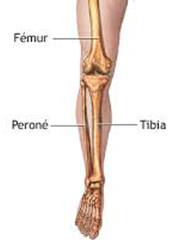

Aunque cada uno de estos huesos puede fracturarse por separado, normalmente la rotura es una lesión que se produce de forma conjunta

Aunque cada uno de estos huesos puede fracturarse por separado, normalmente la rotura es una lesión que se produce de forma conjunta

La mayor parte de las roturas implican a la parte proximal del hueso (parte del hueso próximo a la rodilla) o a la parte distal (parte del hueso cerca del tobillo).

Debido a la fina cobertura de piel que recubre la tibia y el peroné, las fracturas generalmente son abiertas, es decir, el hueso roto rasga la piel, atravesándola. Las fracturas de tibia y peroné generalmente se producen por un fuerte impacto o torsión.